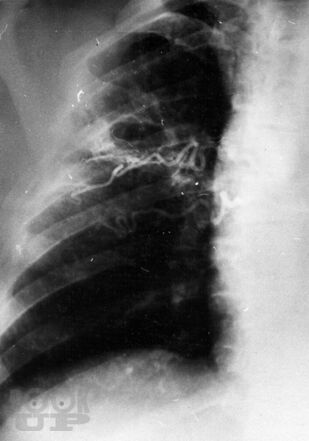

В руководстве представлены современные данные о механизмах развития наиболее частых неотложных заболеваний органов грудной и брюшной полостей, возникающие при них патологические изменения. Подробно изложены методы исследования, диагностики, общие принципы интенсивной терапии, основы предоперационной подготовки пациентов, показания к оперативным вмешательствам, техника их выполнения, принципы послеоперационного ведения больных. Третье издание руководства (второе вышло в 2006 г.) дополнено главами, посвященными неотложным состояниям и хирургической тактике при остро возникших гинекологических заболеваниях, а также получающему развитие методу видеоторакоскопии в неотложной торакальной хирургии.